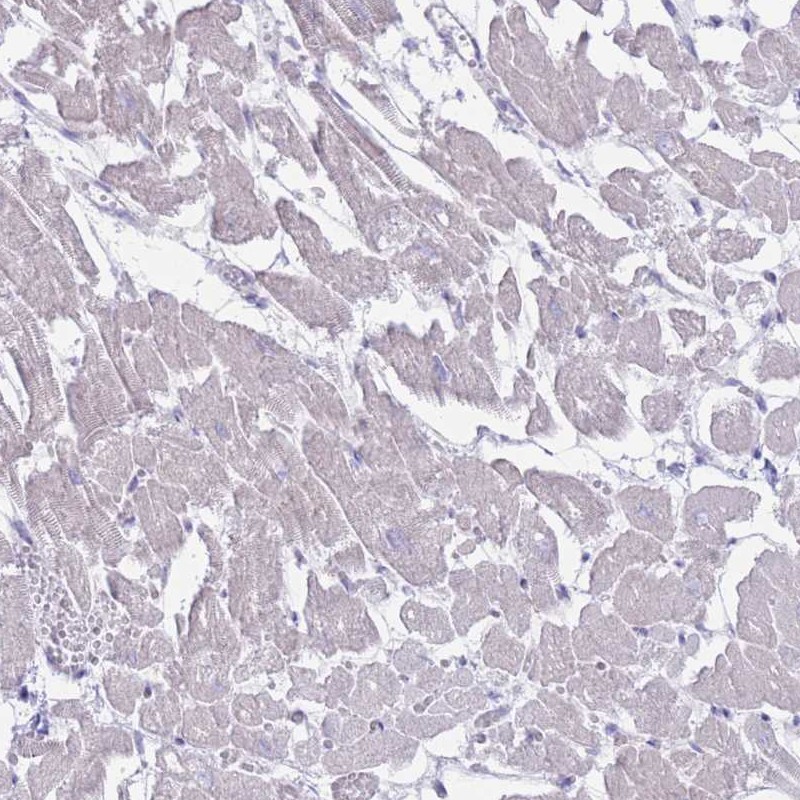

Immunohistochemistry analysis in human skeletal muscle and heart muscle tissues using Anti-MYBPC2 antibody. Corresponding MYBPC2 RNA-seq data are presented for the same tissues.